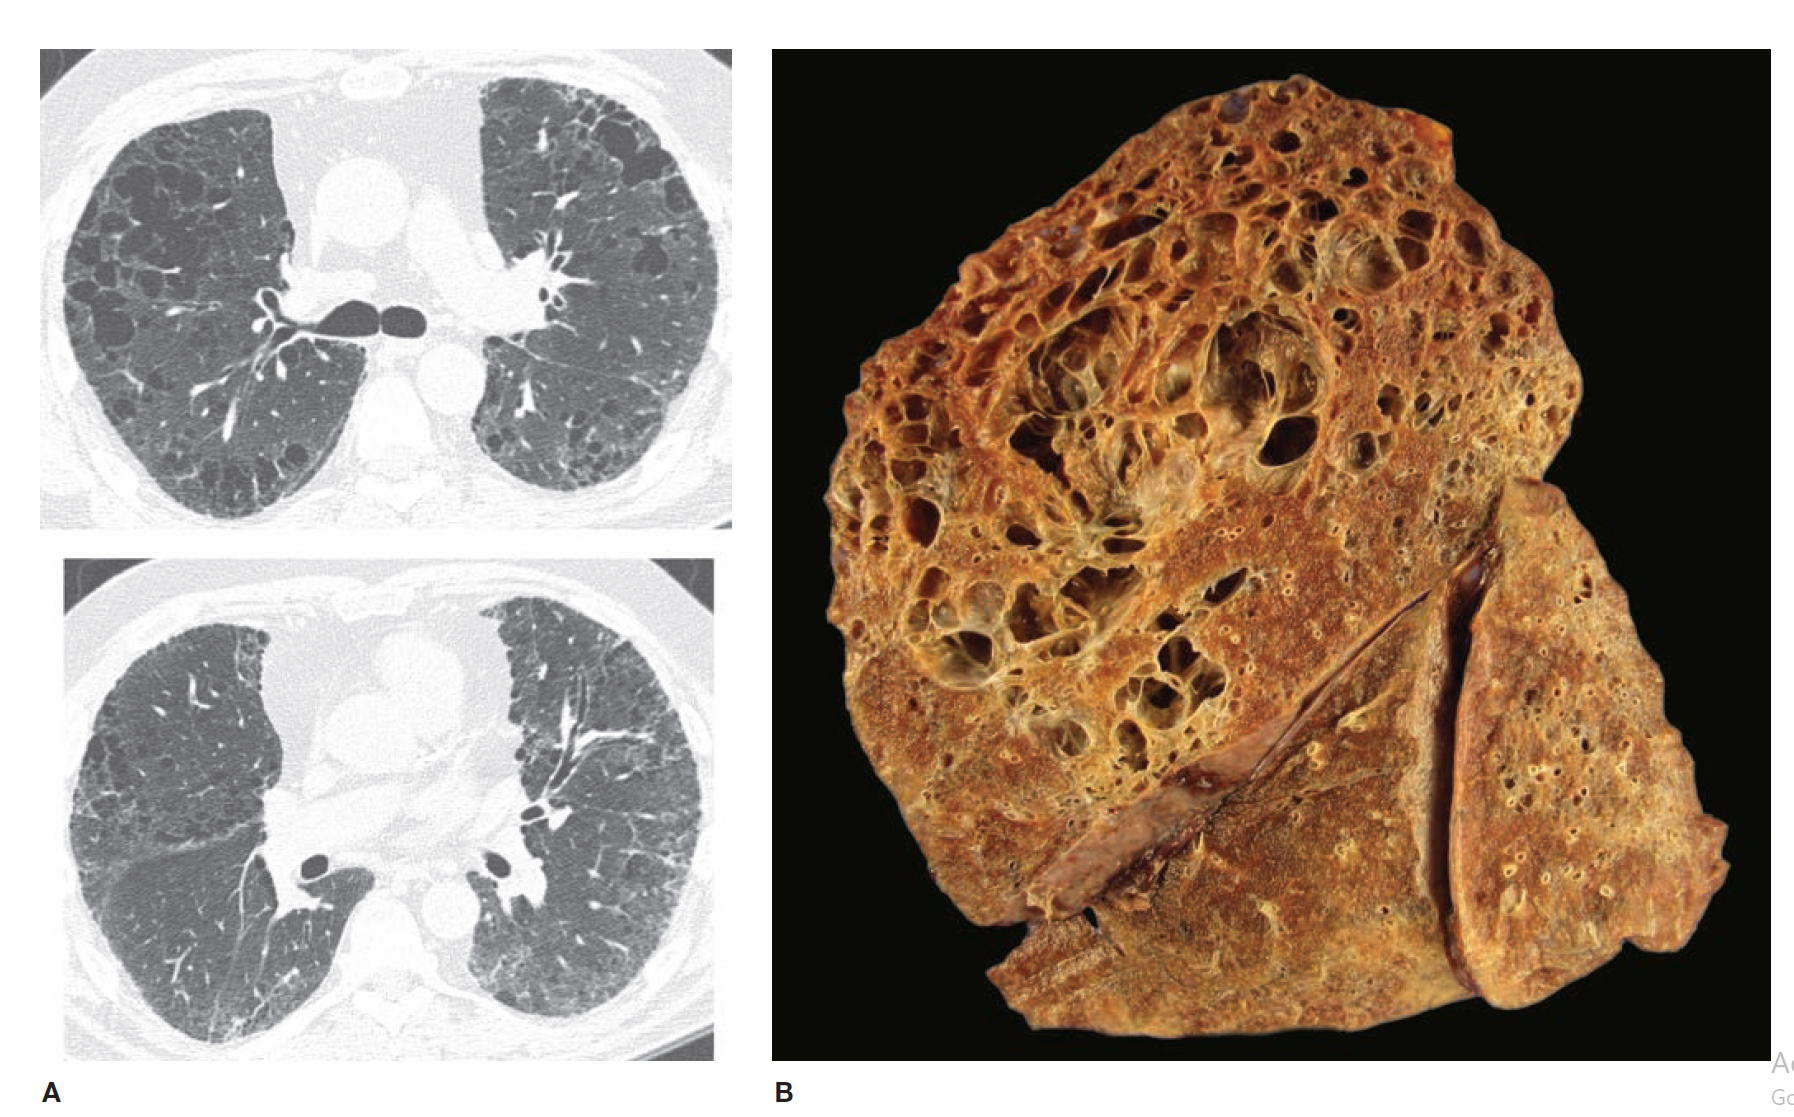

Combined fibrosis and emphysema in a case of chronic (fibrotic) hypersensitivity pneumonitis. A. Computed tomography scan from upper zone (top) shows emphysema and a suggestive of reticulation; lower image from midlung zone shows extensive reticulation indicating the presence of underlying fibrosis. B. Gross photo (sagittal slice) from this case showing marked upper zone emphysema, with fibrosis evident in the most posterior portion of the upper lobe, and the posterior portions of the lower lobe.